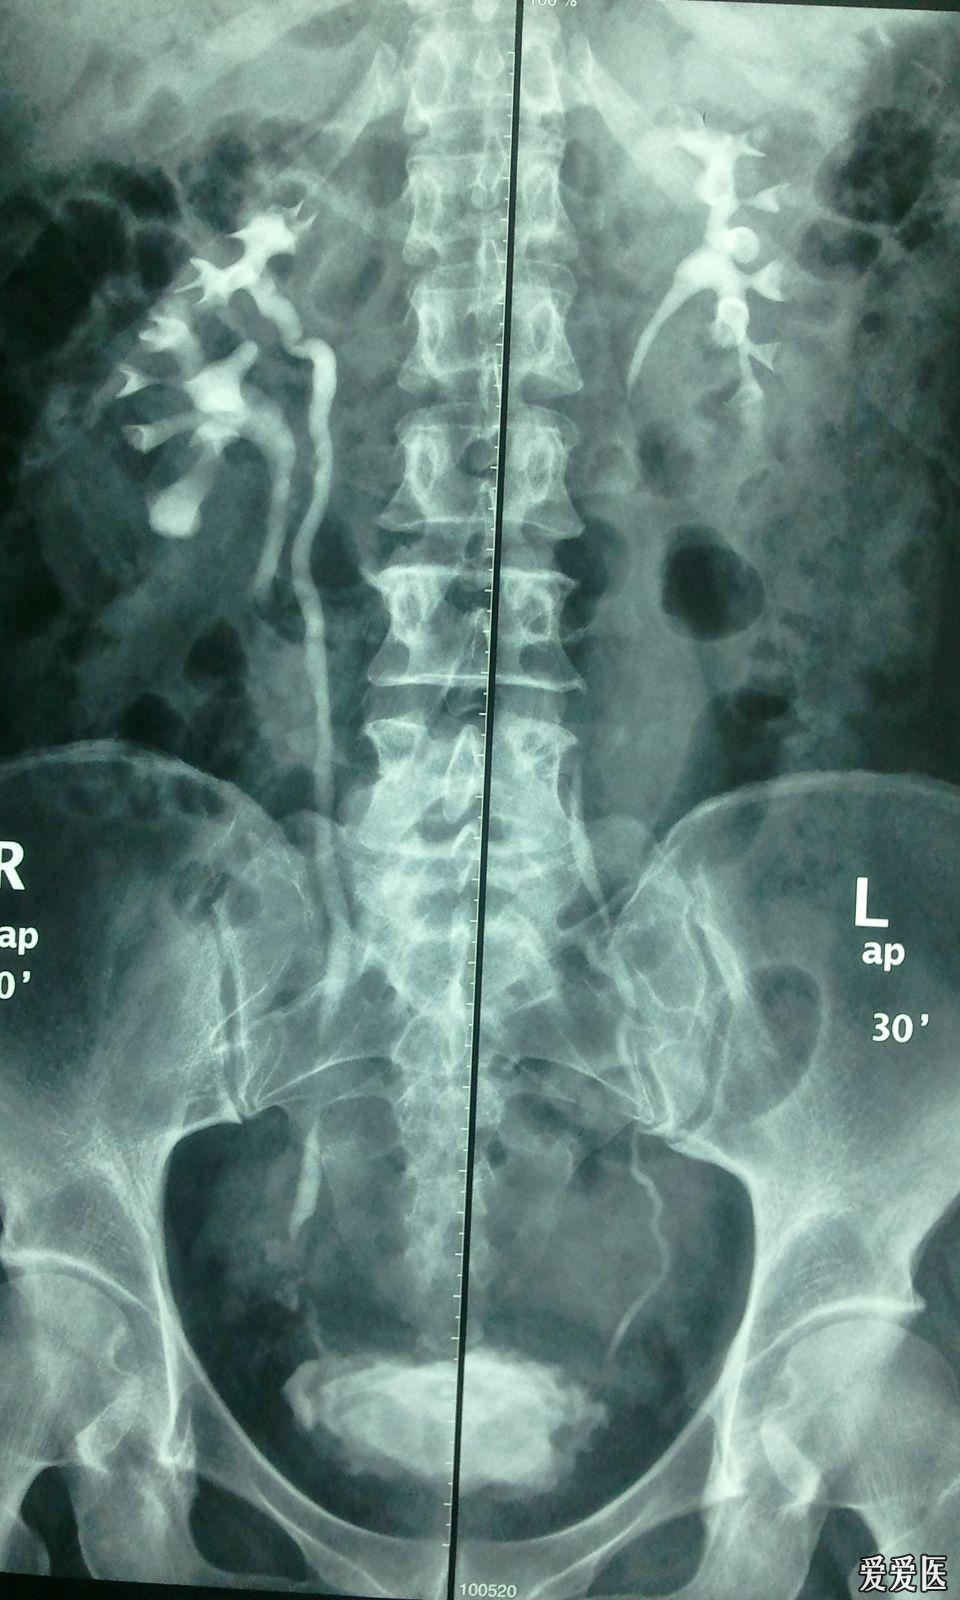

左肾双输尿管畸形右肾盂及上输尿管积水

【贴图】双肾盂,双输尿管畸形